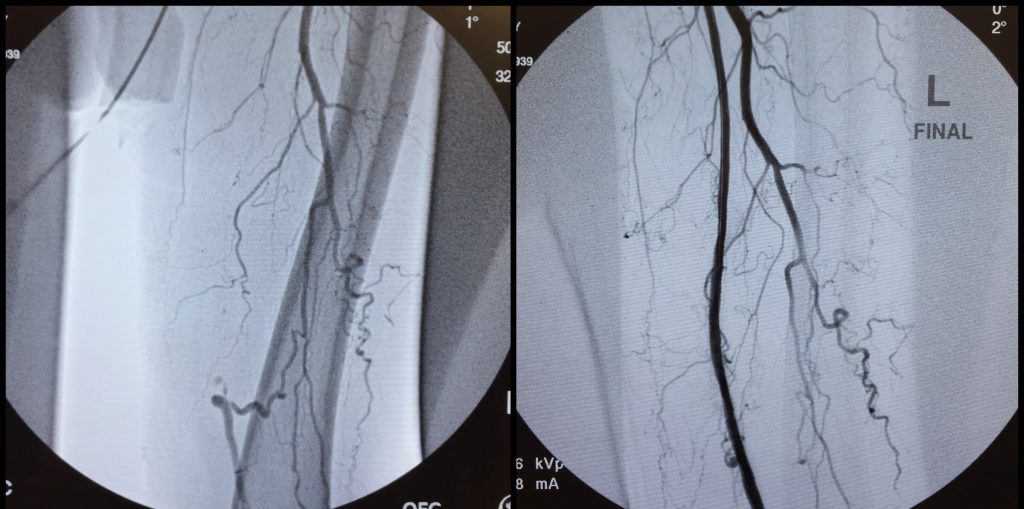

82 year old male with bilateral leg pain at rest and difficulty walking.

The patient had complete blockage of the artery in his right thigh from the groin to the knee.

Dr. Shirey opened the blockage and NO Stents were required.

Compare that with the patient’s left leg which was worked on by another doctor at a local hospital. The left leg has multiple long stents in the patient’s left thigh artery that have clogged after a short time. This is why it’s better to not place such long stents in the leg arteries if possible.